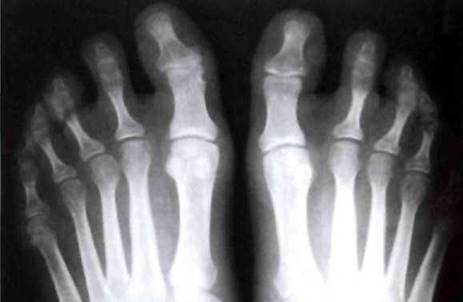

Рис. 23-5. Рентгенограмма стоп больного ювенильным спондилоартритом: деструкция в суставах предплюсны, крупные остеофиты, эрозии, резкое сужение щелей.